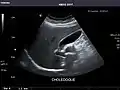

Gallbladder: No stones, wall thickening, or pericholecystic fluid.

Gallbladder